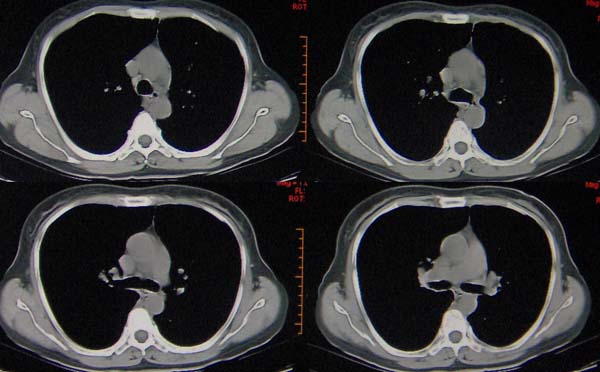

左肺下叶支气管呈囊状扩张。考虑支扩。胸膜肥厚\\粘连,建议增强除外肺隔离症.

肺隔离症伴支扩(肺外型)或肺发育不良。

1,左肺下叶支气管扩张?

2,肺隔离症?

现有的征象提示左肺支扩并双肺炎症。至于隔离肺可以考虑但缺少证据。

双肺炎症;左下支扩并感染,肺隔离症待排

两肺炎症;左下支扩;左下肺副叶!

左肺舌叶及右肺下叶背段斑片状低密度影,左肺下叶内基底段网格状阴影,周围肺野透亮度增高,结合临床咳嗽、发热,38度,无咯血及反复感染病史,考虑双肺炎症,左下肺发育不良。建议抗炎治疗后复查或增强与左下肺隔离症鉴别。